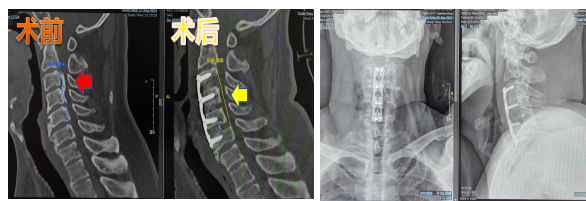

下面分享2个椎体提拉前移术(ACAF)病例:

病例1:

图片6.png

图片7.png

注:患者因颈椎OPLL行走不稳住院,行椎体提拉前移(ACAF)手术,术后脊髓压迫完全解除。

病例2:

图片8.png

注:患者因颈椎OPLL手握力下降行走困难住院,给以椎体提拉前移(ACAF)治疗,术后可见椎体和骨化物已完全提起远离脊髓神经。